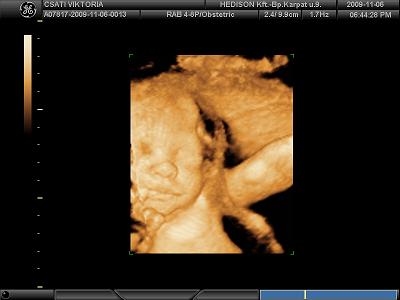

Töltök fel képeket. nekünk csak fekete-fehér van, de legközelebb már kérek színeset, mert megirigyeltem tőletek :)

nagyon bújkált a babánk, szinte végig a hátát láttuk. azért sikerült lefotózni a pofikáját is, de még nagyon ufós :)